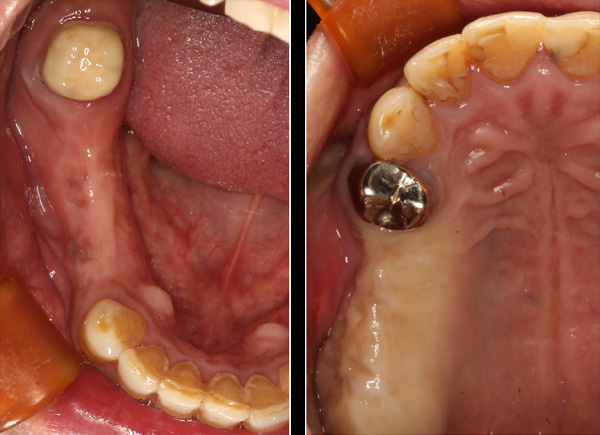

| 年代・性別 | 30代 女性 |

|---|---|

| 主訴 | 左上の乳歯がグラグラしてきた |

| 治療期間 | 約12ヶ月 |

| 費用 | 550,000円 |

| 治療内容 | インプラント、骨造成、セラミック修復 |

| 治療に伴うリスク | インプラント周囲炎 セラミックの破折、脱離 |

*キャンセルポリシーをご一読のうえご予約ください